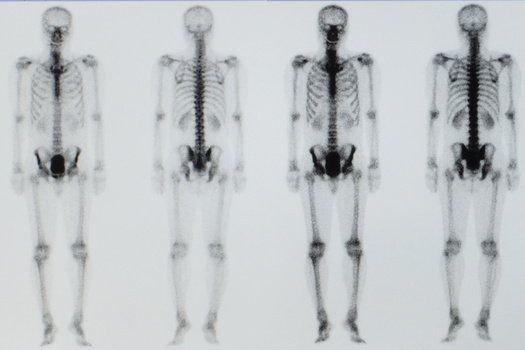

Пациент каждый час поворачивает небольшую ручку этого приспособления, напоминающего аппарат Илизарова, и по чуть-чуть увеличивает промежуток между фрагментами кости. Процедура длится от шести до восьми недель. Кость и окружающие ее мышцы, сухожилия, нервы и кожа едва ли понимают, что их растягивают: для них это просто какой-то очень быстрый рост, и им надо успеть.